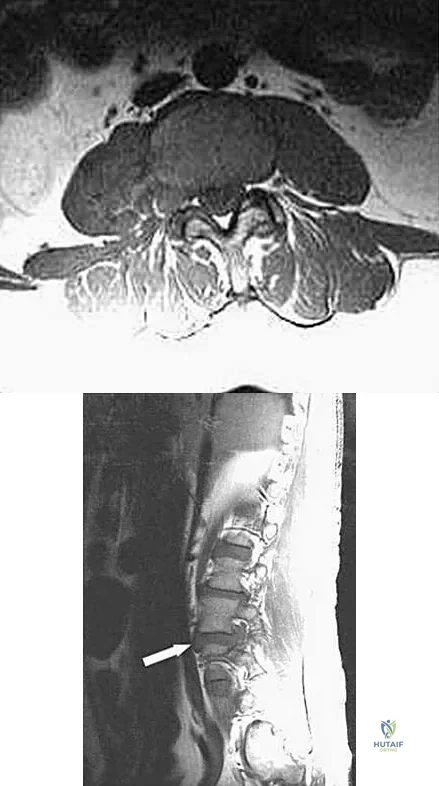

An otherwise healthy 45-year-old woman reports the onset of severe right leg pain. Figure 20a shows an axial MRI scan of the L4-5 level, and Figure 20b shows a sagittal view with the arrow at the L4-5 level. What nerve root is the most likely source of her pain?

Explanation